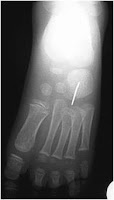

Entre las imágenes más interesantes fue la de las señales de fractura como esta: